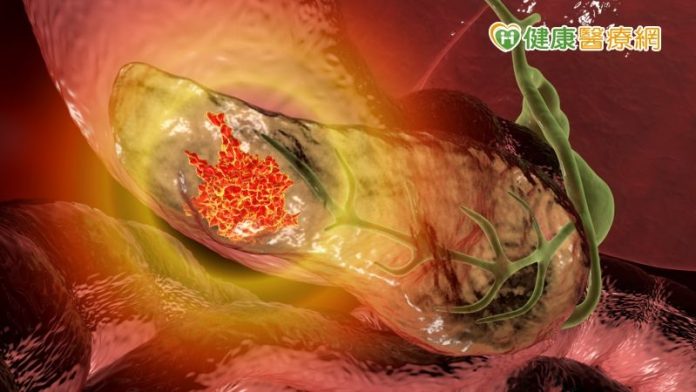

成大醫學院院長暨外科部教授沈延盛表示,胰臟癌近六成確診是晚期,五年存活率約10%,主因是胰臟在腸胃道後方,檢查不易又有腹膜包覆,患者對於疼痛或病變感受不明顯,也常誤以為是腸胃不適,導致出現飯後腹痛、背痛等症狀,往往已是腫瘤壓迫到脾胃血管,疾病進入晚期,預後不佳。

同時,腫瘤亦會影響腸胃道運作,沈延盛院長也曾碰過許多因油便、持續腹瀉,甚至吐血就醫才確診的患者。沈院長進一步說明,由於胰臟癌症狀不明顯,經常與其他疾病混淆,曾有糖尿病患者因血糖持續升高、腹脹卻食慾不振,用藥也不見緩解,延宕了將近半年,最後轉治才發現胰臟癌。